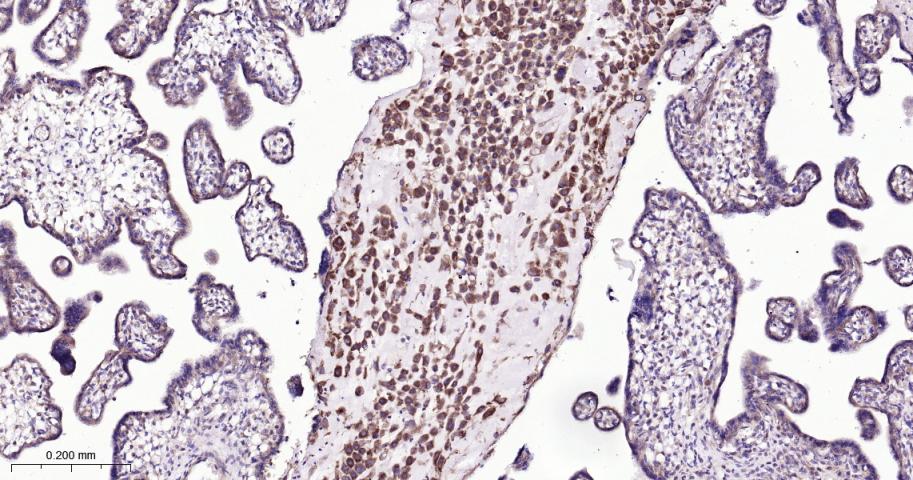

Paraformaldehyde-fixed, paraffin embedded Human placenta; Antigen retrieval by boiling in sodium citrate buffer (pH6.0) for 15 min; Antibody incubation with ATG5 Monoclonal Antibody, Unconjugated(bsm-52596R) at 1:200 overnight at 4°C, followed by conjugation to the bs-0295G-HRP and DAB (C-0010) staining.